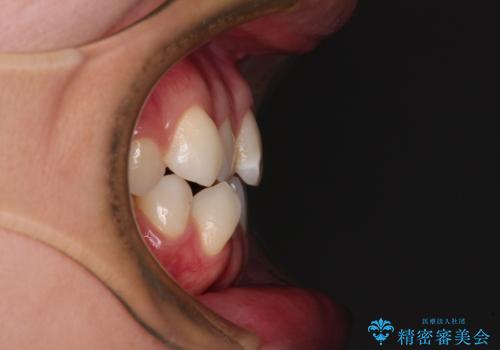

- 前歯のデコボコと奥歯の咬み合わせを気にして来院された患者様です。

右側の奥歯は、上が外側に転位した鋏状咬合を呈しており、前歯のデコボコ改善と並行して咬み合わせを改善していく必要がありました。